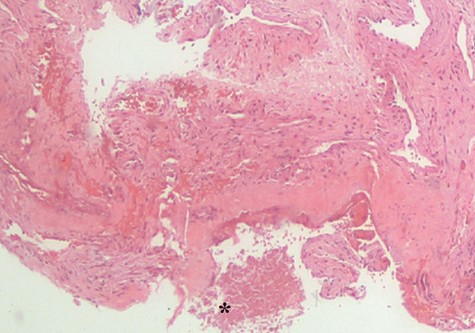

Histopathological examination showed Candida species without evidence of mucosal invasion (Figs. 5 and 6) Intravenous ceftriaxone was commenced for a total duration of 14 days. His symptoms showed significant improvement 1 week after the operation with complete resolution of the headache. His left extraocular muscle functions were slowly restored at 4 weeks post-operation (Fig. 7).

Histopathological examination revealed fungal body (*). No evidence of mucosa invasion was observed.